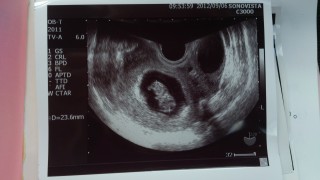

CRL:23ミリ☆

23.5mmで順調です(≧∇≦)